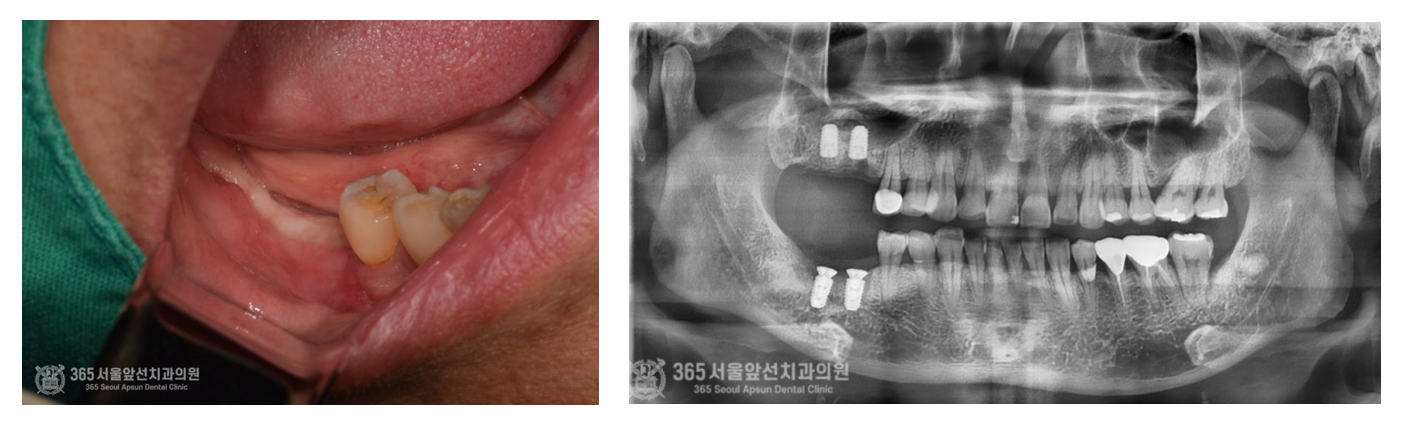

촬영일자:24.05.09 발치 후 체크약속때 엑스레이 사진입니다. 해당측의 치아들은 이미 잇몸뼈의 소실이 너무 심각하여 사용할 수 없는 수준이었기에 신경이 손상되지 않도록 조심스럽게 발치를 진행하였습니다.

촬영일자:24.08.30 좌측 사진 보시면 뼈이식이 끝난 후 회복과정에서 촬영한 구강내 사진입니다. 잇몸이 깨끗하게 아물고 있습니다. 또한 우측사진은 임플란트 치료 진행 중 촬영한 엑스레이입니다. 임플란트와 이식된 뼈가 잘 굳어가고 있죠.